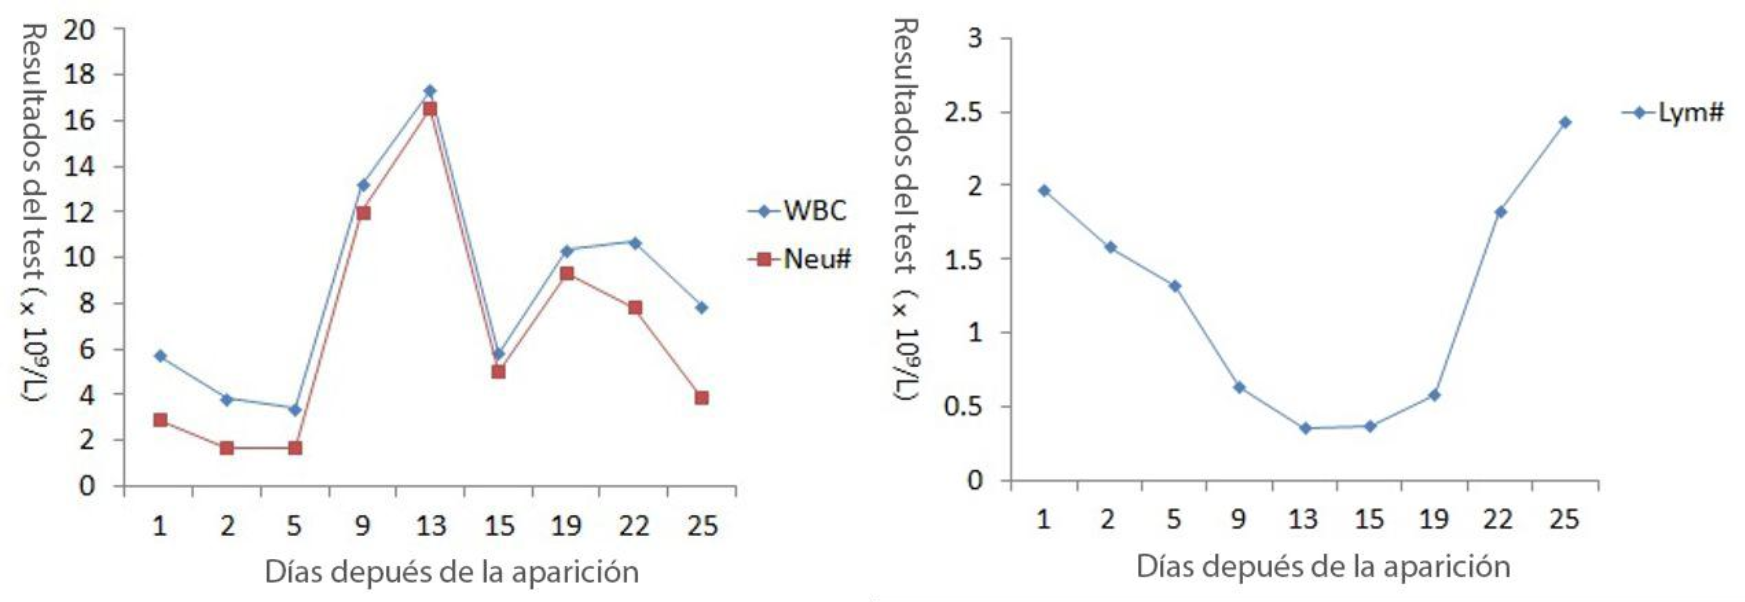

Durante todo el proceso de diagnĂłstico y tratamiento, se han registrado las manifestaciones clĂnicas del paciente y los resultados de la tomografĂa computarizada del tĂłrax (ver Tabla 1), y tambiĂ©n los resultados de CBC y CRP (ver Figura 1).

A medida que la salud del paciente se deteriorĂł, el recuento de glĂłbulos blancos (WBC #) y el recuento de neutrĂłfilos (Neu #) aumentaron bruscamente despuĂ©s de una ligera disminuciĂłn, mientras que el recuento de linfocitos (Lym #) continuĂł disminuyendo. La relaciĂłn de neutrĂłfilos a linfocitos (NLR) aumentĂł rĂĄpidamente mientras que el valor de la PCR aumenta. En el momento mĂĄs crĂtico (el dĂa 13 despuĂ©s del inicio de los sĂntomas), WBC #, Neu #, NLR y CRP alcanzaron sus picos respectivamente, con Lym # en el punto mĂĄs bajo.

DespuĂ©s de un tratamiento mĂ©dico y cuidados adecuados, el paciente se recuperĂł gradualmente, con una rĂĄpida disminuciĂłn de WBC #, Neu #, NLR y CRP. En contraste, Lym # aumentĂł gradualmente. El dĂa 25, WBC #, Neu #, NLR, Lym # y CRP volvieron al rango normal. Aunque la tomografĂa computarizada mostrĂł que las lesiones en los pulmones aĂșn no habĂan desaparecido por completo, el paciente ya podĂa moverse sin oxigenoterapia. Lo mĂĄs importante, el resultado de la prueba de ĂĄcido nucleico se volviĂł negativo.